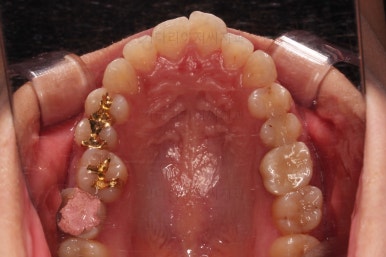

윗니도 발치를 했고요.

발치공간을 서서히 줄여 나갑니다.

입매 변화도 신중하게 체크합니다.

윗니는 어느 정도 틈이 많이 줄었는데요. 아랫니는 기약이 없죠.

이제 미니스크류가 등장합니다.

상하좌우 발치 공간의 크기와 위치가 제각각이라서 당겨지는 양과 속도가 차이납니다.

그래서 미니스크류를 반드시 써줘야 합니다.